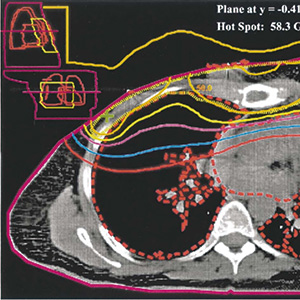

中等风险乳腺癌患者 术后胸壁放疗不改善预后

英国爱丁堡大学Kunkler等报告的针对1607例患者随访10年的结果显示,中等风险乳腺癌患者乳房切除术后胸壁放疗并未改善总生存和复发风险,研究结果不支持中等风险患者术后放疗。(N Engl J Med. 2025, 393: 1771.)中等风险指病理分期为pT1N1、pT2N1或pT3N0的癌症,或病理分期为pT2N0且伴有组织学分级3级和/或淋巴血管侵犯的癌症。研究在172个国际中心开展,患者入组条件为单侧Ⅱ期、中等风险接受乳房切除术,无远处转移,切缘净距至…